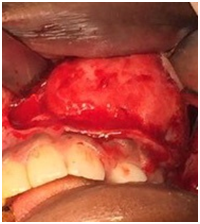

The surgical excision of the cyst was done under general anaesthesia along with the removal of the unerupted canine and sent for the histopathology lab which confirm the diagnosis of (AOT) (Figure 4-6). The patient has been under follow-up for one year and was rehabilitated with fixed prosthesis.

Figure 4 Surgical bed, well-circumscribed tumor covered by a thin layer of indurated grayish membrane within the maxillary sinus.